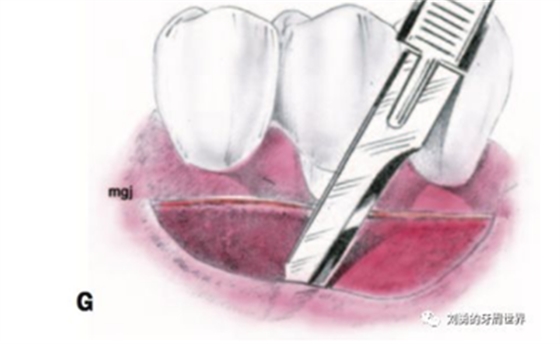

5、刀片向根向繼續(xù)分離半厚瓣,冠根向延伸6-8mm,注意避讓頦神經(jīng),翻開半厚瓣如下圖:

6、剪刀去除殘留的條狀牙槽粘膜(I),骨膜床預備結束(J)

7、剪刀去除骨膜上剩余的肌肉組織纖維(K),可以將翻開的半厚瓣剪掉或根向縫合在前庭溝的骨膜上。